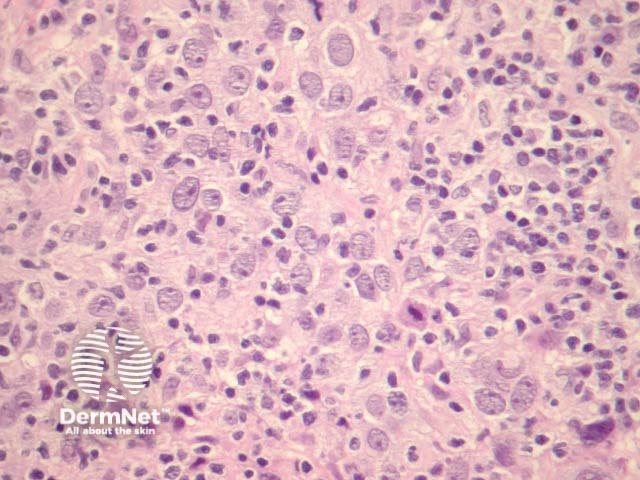

In lymphoepithelioma-like carcinoma, sections show atypical epithelioid cells forming well-defined nests surrounded by dense lymphocytic inflammation. High-power view shows a poorly differentiated carcinoma with lymphocytic infiltration (figures 1-3). Perineural, lymphovascular and subcutaneous invasion is common.

Figure 1